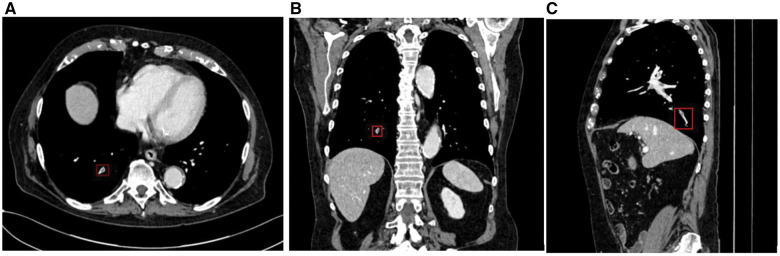

Materials and methods: A commercially available deep learning-based software, CINA-iPE (Avicenna.AI, La Ciotat, France), analyzes CECT images to highlight suspected incidental PE cases. Consecutive retrospective CECTs from 5 clinical centers, not performed for PE evaluation, were collected until a selected balanced dataset between positive and negative cases was obtained. The reference standard was established by three independent U.S. board-certified radiologists reviewing the same images. Diagnostic performance and the time-to-notification (from data acquisition to processing of results) were computed.

Results: A total of 381 anonymized CECT cases were acquired on 39 different scanner models from GE, Philips, Siemens, and Canon. The algorithm correctly identified 159/181 exams positive for PE (sensitivity 87.8% [95% CI: 82.2%-92.2%]) and 184/200 exams negative for PE (specificity 92.0% [95% CI: 87.3%-95.4%]), yielding an accuracy of 90.0% [95% CI: 86.6%-92.8%]. Of 16 detected false positive cases, 50% were complex CECTs subject to disagreement among the reference read radiologists. The device missed 22 pulmonary embolisms, with 45.5% of them being complex cases and subject to disagreement among reviewers. The time from data acquisition to processing results was 1.5 ± 0.5 (mean ± SD, 95% CI: 1.4%-1.5%) minutes.